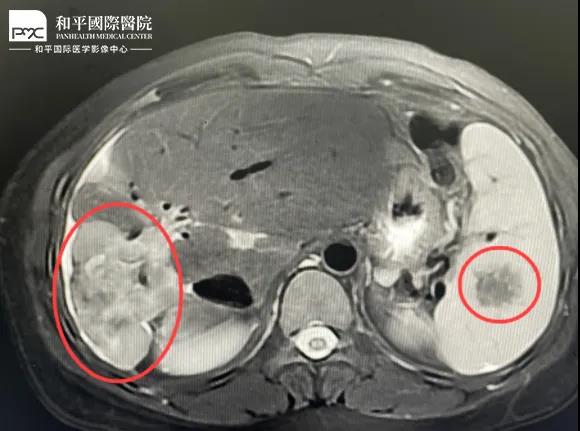

檢查結(jié)果對于這家人而言猶如晴天霹靂,經(jīng)核磁共振等相關(guān)檢查,當(dāng)?shù)蒯t(yī)生懷疑是肝癌,建議手術(shù)治療。悲痛中,家人們對這樣的結(jié)果表示無法接受,想要多去幾家醫(yī)院看看,為了進(jìn)一步確診,王小姐來到我院醫(yī)學(xué)影像中心進(jìn)行檢查,事情竟發(fā)生了戲劇性反轉(zhuǎn)。

根據(jù)影片分析,結(jié)合王小姐有系統(tǒng)性紅斑狼瘡的病史,長期服用激素,免疫力低下,近期又有低熱盜汗的癥狀,影像中心執(zhí)行主任侯文杰初步判斷王小姐是得了肝結(jié)核,并不是肝癌!

由于肝結(jié)核是臨床非常少見的病例,單靠影像診斷是很難診斷正確的,在侯主任的建議下,王小姐做了穿刺活檢,診斷結(jié)果的確是肝結(jié)核。